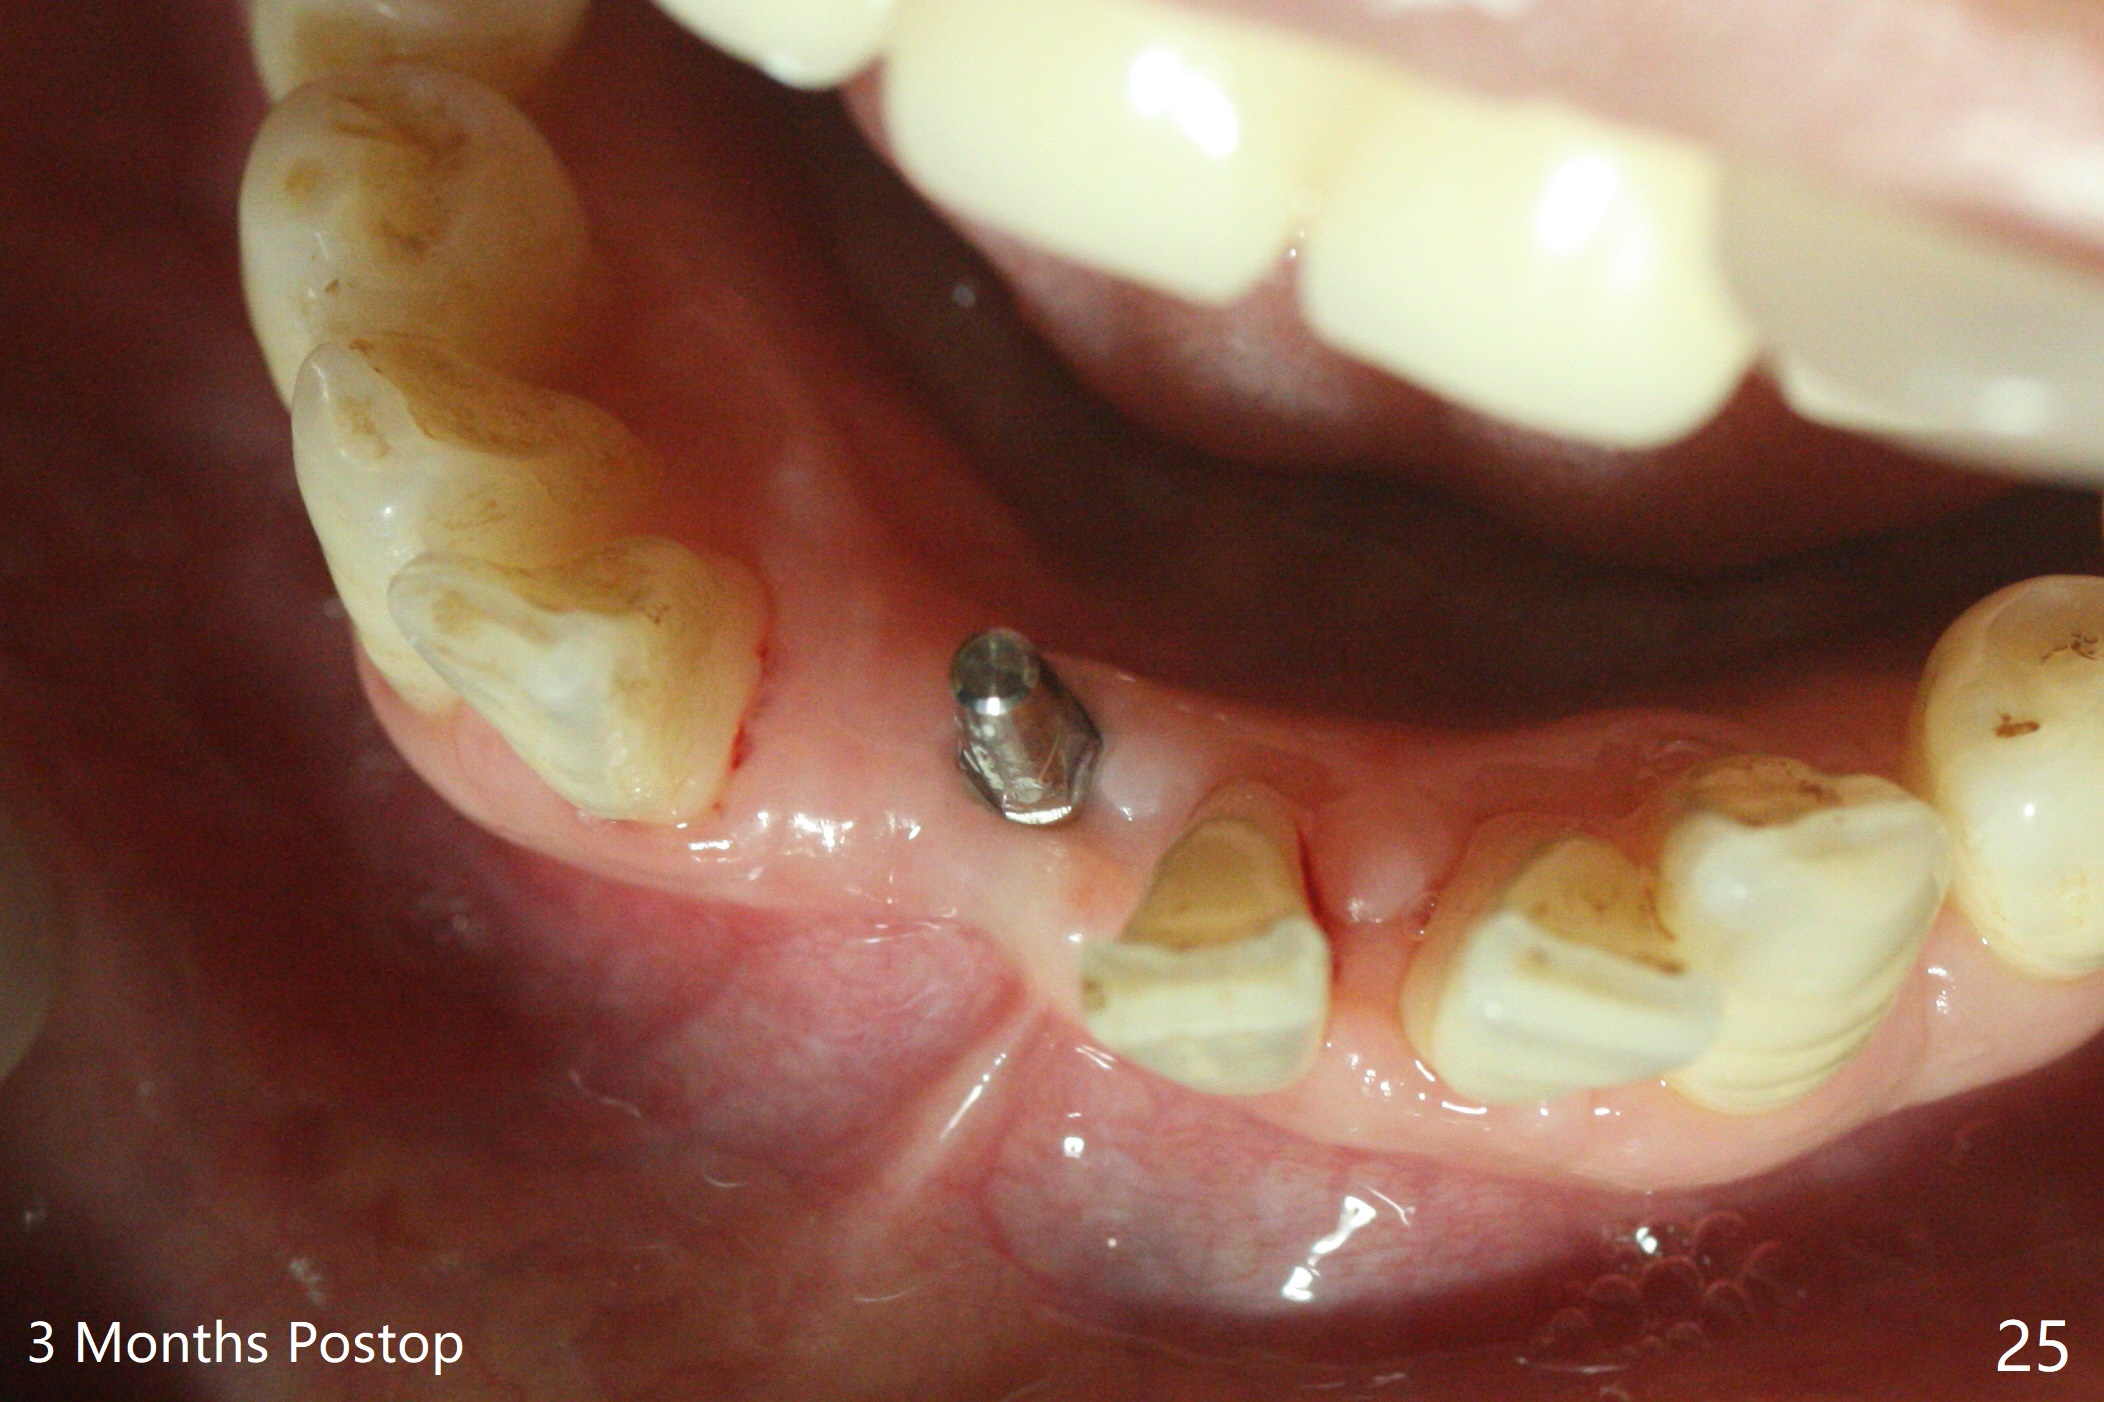

56岁女十分恐惧治疗,缺失右下1,其余切牙由于骨质吸收颊侧移位(图一:1,2),但是她不愿意拔除,同意右下1种植,牙周骨手术,植骨;植体整合后作为支抗,矫正移位下门牙。为了防止忘记舌侧瓣分离,先做舌侧切口(图二),然后颊侧瓣松弛分离(图三),包括使用前牙隧道刀(图四)切断颊侧骨膜,松弛到颊侧瓣能向舌侧牵拉3-4毫米(图五),舌侧瓣骨膜下广泛,深部分离(好像不能切断骨膜,图六),放置导板,磨平狭窄的牙槽嵴(图七:O(osteotomy)),植入2.5x12(4)毫米一段式植体(图八:故意舌侧植入,以便以后矫正),在颊侧骨板打多个出血洞(图八:箭头),然后把在平的器皿上形成的粘性骨板(sticky bone,图九),放置于植体和移位切牙周围(图十),接着使用消毒过的橡皮障punch(图十一(纸头相当于PRF膜;事先给助手示范))在三个PRF膜(图十二)打洞,套在植体和门牙上(图十三: 箭头),防止膜(图十四)和骨块(图十五,十六:*)移位,最后还必须使用最原始方法牙周敷料保护伤口(图十七)。术后9天,舌侧牙周敷料脱落,伤口稍微裂开(图十八)。术后18天撤除敷料,伤口裂开处有新鲜肉芽组织生长(图十九(*:下面是填入的骨粉,将是增宽的牙槽嵴(如果你是乐观主义者)),二十)。病人十分感激我们帮助她度过难关。她的确有sleep apnea,否定tongue thrust。术后三个月植体周围没有明显骨质吸收(图二十一至二十三),左下1,2轻度反合(图二十四),植体周围软组织健康(图二十五),5-5安置矫正器(图二十六,二十七,12 niti)。一周后下切牙向舌侧移动(图二十八),左下1,2反合纠正(图二十九)。再一周变化不大(图三十),植牙圈有些松动,两周后将重做临时牙冠,槽往舌侧移动。结果病人提前回来,植牙槽舌侧移位。一周后右下2不适(图三十一),尝试近中牵引(图三十二)。